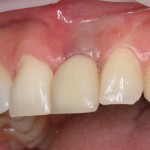

Обратите внимание на состояние вестибулярной стенки лунки. В проекции верхушек корней вы можете увидеть костный дефект, вызванный длительным воспалительным процессом (собственно, почему этот зуб пришлось удалять). В этом случае, вестибулярная стенка лунки неизбежно лизируется после удаления зуба, а это приведет не только к проблемам в эстетике, но и осложнит последующий уход за протетической конструкцией. Поэтому в данном случае мы должны продумать, в том числе, аугментацию лунки. И порядок действий здесь несколько иной, нежели в предыдущем случае.

Устанавливается имплантат Astratech (Dentsply Implants):

Для аугментации также используем Bio-Oss Collagen 100 mg, нарезаем его по размеру с помощью скальпеля и позиционируем в лунках щечных корней:

На имплантат ставим формирователь, ушиваем лунку. Напомню, что любой биоматериал должен быть герметично запечатан в ране (фактор успеха III). В противном случае, от него больше вреда, чем пользы: